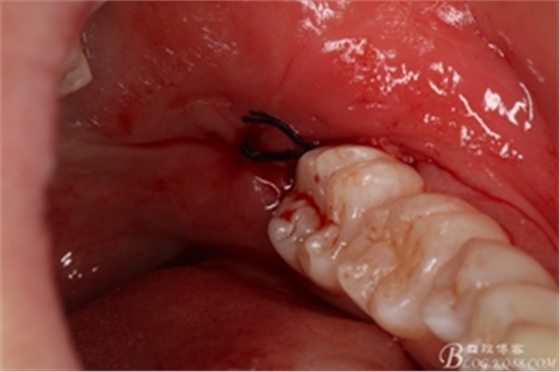

圖17. 縫合